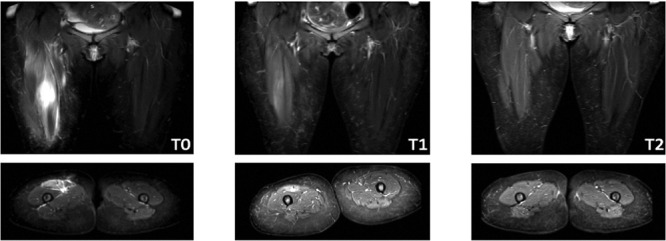

急性肌肉疼痛是指在剧烈运动期间或 24 小时内出现的肌肉酸痛。急性肌肉疼痛的可能原因包括局部肌肉创伤、肌肉撕裂、急性出血挫伤或急性隔室综合征。股直肌孤立性断裂是一种罕见的临床病症,是由于肌肉突然收缩、不正确的运动或突然扣动后过度拉伸,超过了肌肉所能承受的生理极限。迄今为止,很少有公开报道对此类损伤的非侵入性治疗效果进行评估。在此,我们报告了一例不寻常的孤立性股直肌远端撕裂病例,患者是一名 46 岁的女性,无任何危险因素,最初表现为伸肌无力和疼痛,接受了功能性休息、理疗和冷冻疗法等保守治疗。

Acute muscle pain is muscle soreness that occurs during or within 24 hours of strenuous activity. Possible causes of acute muscle pain include localized muscle trauma, muscle tear, contusion with acute hemorrhage, or acute compartment syndrome. Isolated ruptures of the rectus femoris muscle are rare clinical conditions that result from excessive muscle strain following an abrupt contraction, incorrect movement, or sudden snap that exceeds the physiological limit of strain that the muscle can withstand. To date, there are few published reports evaluating the results of non-invasive treatment of such injuries. Herein, we report an unusual case of isolated distal rectus femoris tear in a 46-year-old female patient with no risk factors, who initially presented with extensor muscle weakness and pain and was treated conservatively with functional rest, physiotherapy, and cryotherapy.